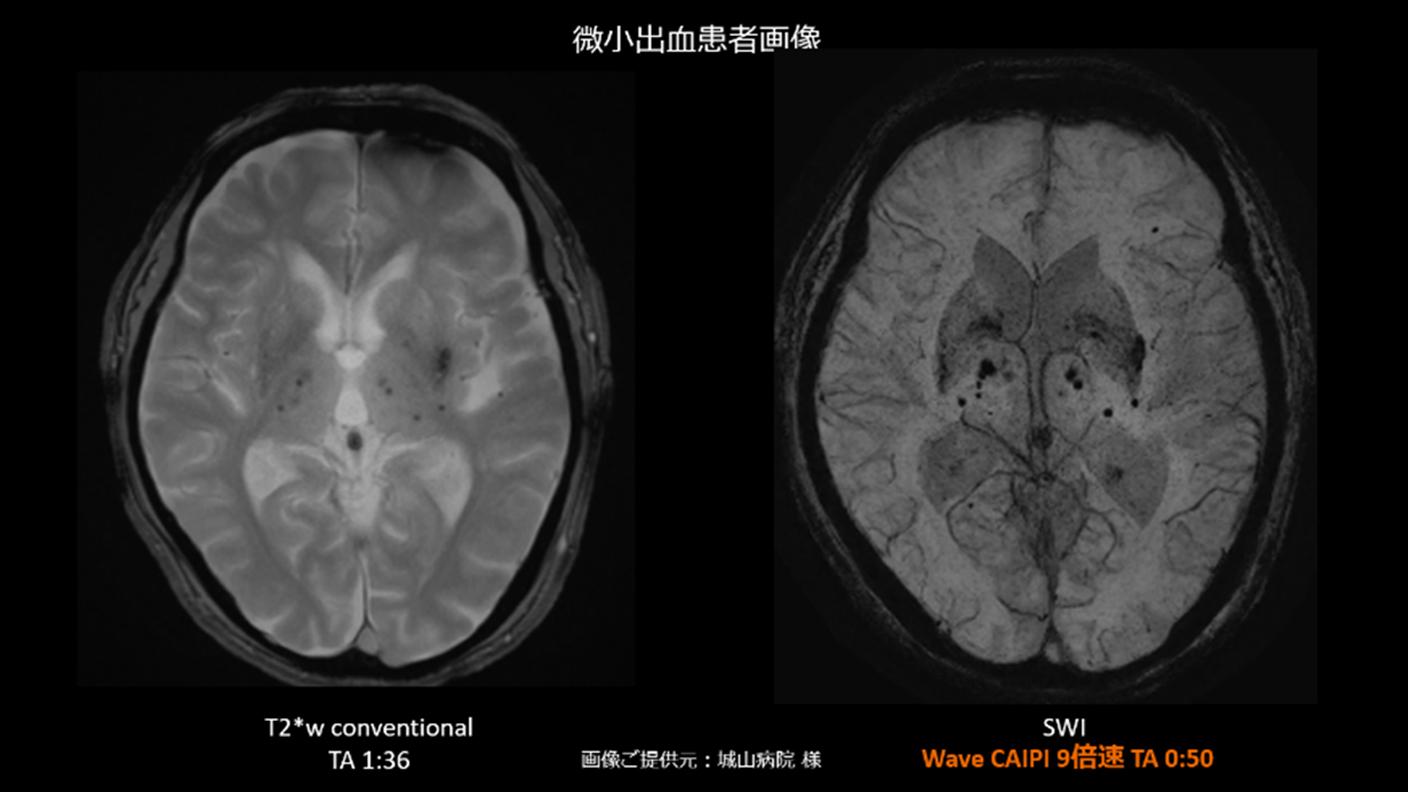

Stroke(脳卒中領域)

非造影で脳血流・血管・血管壁を高精度に評価する技術で、急性期の虚血評価から治療後フォローアップ、再発リスク層別化まで、脳卒中診療の質向上に貢献します。